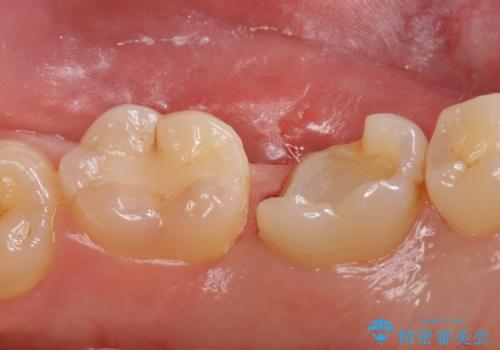

詰め物が欠けてしみる

- 過去に他院で治療した詰め物が欠けてしみるとの事で来院。

プラスチックの樹脂での治療(保険)でされており虫歯が再発していました。

あまり歯質を削って欲しくないとの事だったのでゴールドインレーでの治療になりました。

セラミックの詰め物は範囲が多ければ多いいほど割れてしまうリスクが高いため

被せ物(ジルコニアクラウン)のご提案をさせて頂く場合があります。

今回はなるべく歯質を残したいとの事なのでゴールドの詰め物でご案内させて頂きました。ゴールドは範囲が多くても割れる心配がありません。また、虫歯の再発リスクが低いです。